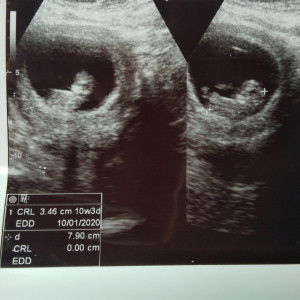

mom risau

Hye moms..nak tnya nie skrg sya ngandung 10 week..da dkt 2 mggu sya cirit birit..da p klinik dan da mkn ubat tpi masi xjln..mcm tu juga kisahnya masi cirit birit..adaka nie sala satu alahan juga?sapa ada pngalaman mcm sya dan pa yg perlu sya buat..bdn da lemas sngt2